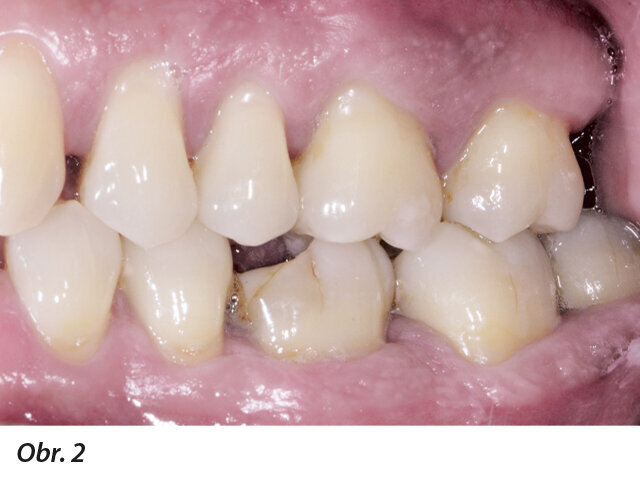

Obr. 1–5: Fotografi cká dokumentace počátečního stavu před parodontologickým ošetřením

49letý pacient přišel na naše oddělení se stížností na krvácení dásní a rozestupování frontálních zubů (obr. 1–5).